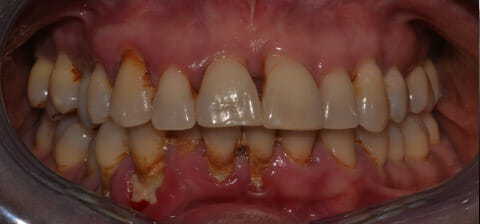

Endorale prima e dopo la cura della parodontite

Con terapia parodontale fotodinamica non chirurgica: si noti la ricrescita naturale dell’osso e del tessuto parodontale.